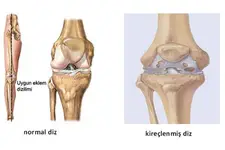

Fibröz kıkırdak, travma veya aşınma sonucu zarar görebilir. Bu tür durumlarda, kıkırdak onarım süreçleri yavaş ilerleyebilir ve genellikle cerrahi müdahale gerektirebilir. Fibröz Kıkırdak Hastalıkları Fibröz kıkırdak ile ilişkili bazı hastalıklar ve durumlar şunlardır:

Bu hastalıkların tedavisi genellikle fizik tedavi, ilaç tedavisi ve cerrahi yöntemleri içerir. Sonuç Fibröz kıkırdak, vücudun destek ve hareket sisteminde kritik bir rol oynamaktadır. Yapı ve fonksiyon özellikleri sayesinde, çeşitli anatomik yapılar içinde önemli işlevler üstlenir. Fibröz kıkırdağın sağlığını korumak, genel fiziksel sağlık açısından önemlidir. Beslenme, egzersiz ve uygun tedavi yöntemleri ile fibröz kıkırdak sağlığı desteklenebilir. Ekstra Bilgiler Fibröz kıkırdağın onarım süreçleri, yaşla beraber yavaşlayabilir. Bu nedenle, yaşlanma sürecinde eklem sağlığını korumak için düzenli egzersiz yapmak ve sağlıklı beslenmek oldukça önemlidir. Ayrıca, fibröz kıkırdak sağlığını korumak için anti-inflamatuar besinlerin tüketilmesi önerilmektedir. Omega-3 yağ asitleri ve antioksidanlar bu bağlamda faydalı olabilir. Fibröz kıkırdak ile ilgili araştırmalar, bu dokunun onarım ve rejenerasyon potansiyelini artırma yönünde devam etmektedir. Gelecekte, biyomühendislik ve hücresel tedavi yöntemleri ile fibröz kıkırdağın onarımını sağlamak mümkün hale gelebilir. |